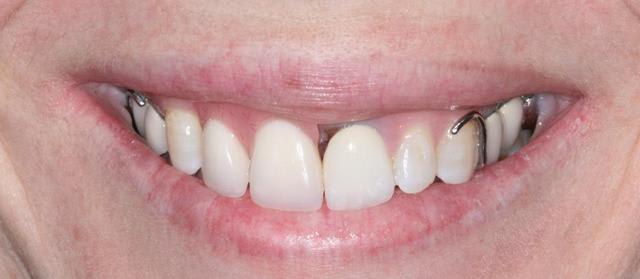

Bon finalement je vous poste le cas terminé.

La prochaine fois je ferrai une greffe d'apposition comme j'avais pu le préssentir... Ca me permettra de garder les papilles.

A la prochaine séance je gomme la coloration mésiale de 12, c'est promis ;+)

Un cas pas évident... l'important est que la patiente soit contente à la fin.